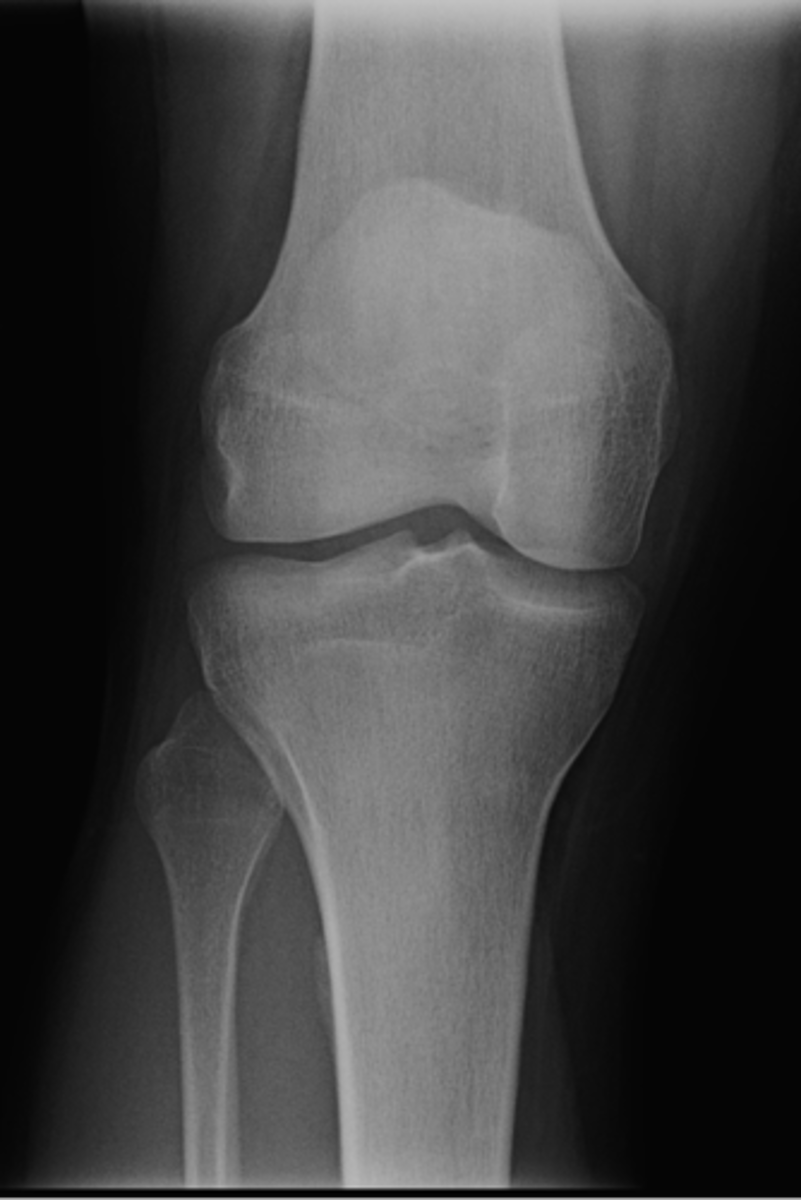

AP knee

ID standard knee projection

<p>ID standard knee projection</p>

82

New cards

Lateral knee

83

Flexion

Lateral knee projections are generally taken with _____

<p>Lateral knee projections are generally taken with _____</p>

84

Tunnel (intercondylar) knee

85